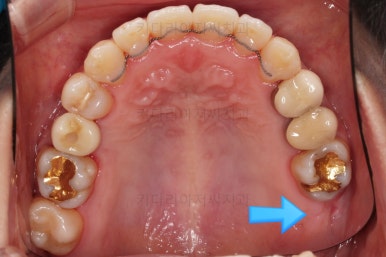

임플란트 보철이 깔끔하게 들어갔고, 교정치료도 마무리가 되었습니다.

화살표 부분은 임플란트가 안들어갔는데요.

약간의 우여곡절이 있긴했었지만 엄밀히 따지면 위아래가 지그재그로 껴들어가는 교합의 특성상 윗니는 1개 모자라도 교합에는 크게 문제가 없답니다.

해당 부분을 임플란트를 해주면 좋겠지만 환자분도 충분히 고민 후에 원하실 때 식립을 하기로 마무리르 하였습니다.